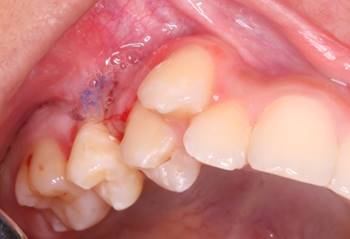

The intraoral clinical examination showed a tumor-like lesion that was painful to palpation and chewing at the marginal and alveolar gingiva level of teeth 1.4 and 1.5 (Fig. 1), approximately 3x3x3 cm in diameter, covering the buccal and palatal areas, and part of the clinical crown. Its consistency was firm, lobular, and pedunculated. It had a rough and bleeding texture when stimulated, with grade II mobility in tooth 1.4 (Fig. 2). The radiographic examination showed the alveolar crest’s effacement between teeth 1.5 and 1.4, with mesioangular and widened periodontal space 1.4 (Fig. 3). The presumptive diagnosis was pyogenic granuloma or peripheral giant-cell granuloma based on the evolution and clinical characteristics.

Figure 2: A: Front view of the lesion covering the buccal faces of teeth 1.4 and 1.5. B: Occlusal view of the lesion covering the palatal faces and part of the clinical crown of teeth 1.4 and 1.5